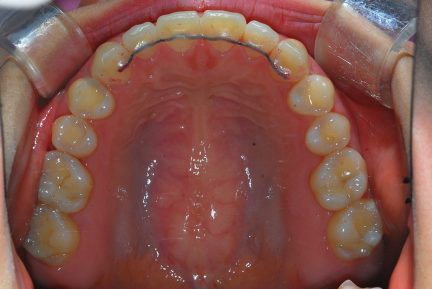

État final

Commentaires

- Une expansion précédente du maxillaire a été effectuée.

- Après l'expansion, ce cas a été préparé pour la chirurgie orthognatique.

- Seul Invisalign sans autre appareil et sans besoin d'élastiques a été utilisé pour la préparation.

- Une surcorrection de l'articulé croisé postérieur a été planifiée pour s'assurer que nous n'aurions pas de contacts prématurés dans la période postopératoire immédiate.

- Entre 3,4 et 3,5, nous n'avons fait qu'une réduction interproximale de 0,3mm pour renforcer la fermeture des espaces.

- La petite déviation médiane a été corrigée avec des aligners supplémentaires.

- La dent 1,7 a été extraite car elle n'avait pas d'antagoniste et le patient ne souhaitait pas poser d'implant dans la région de 4,7